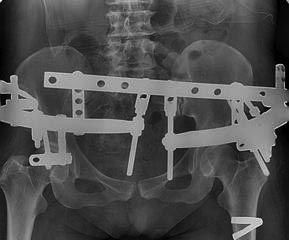

АВФ

Как экстренная и временная стабилизация - лучше не получится и это допустимо. Главное - экстренно объем полости малого таза уменьшен.

В данной ситуации повреждение тазового кольца типа С.

При разрыве КПС фиксация переднего полукольца порочна, вы "расхлопнули" заднее полукольцо.

Если опоры на крыльях таза стабильные, ввести пациент в наркоз, размонтировать узлы между опорами, наложить скелетное вытяжение за мыщелки бедра килограмм 20-25 постепенно, дать повисеть, рентгеноконтроль. Все это можно делать в ПИТ. Смонтировать узлы между опрорами.

Дальше между опорами монитовать репозиционные узлы и "закрывыть" таз.